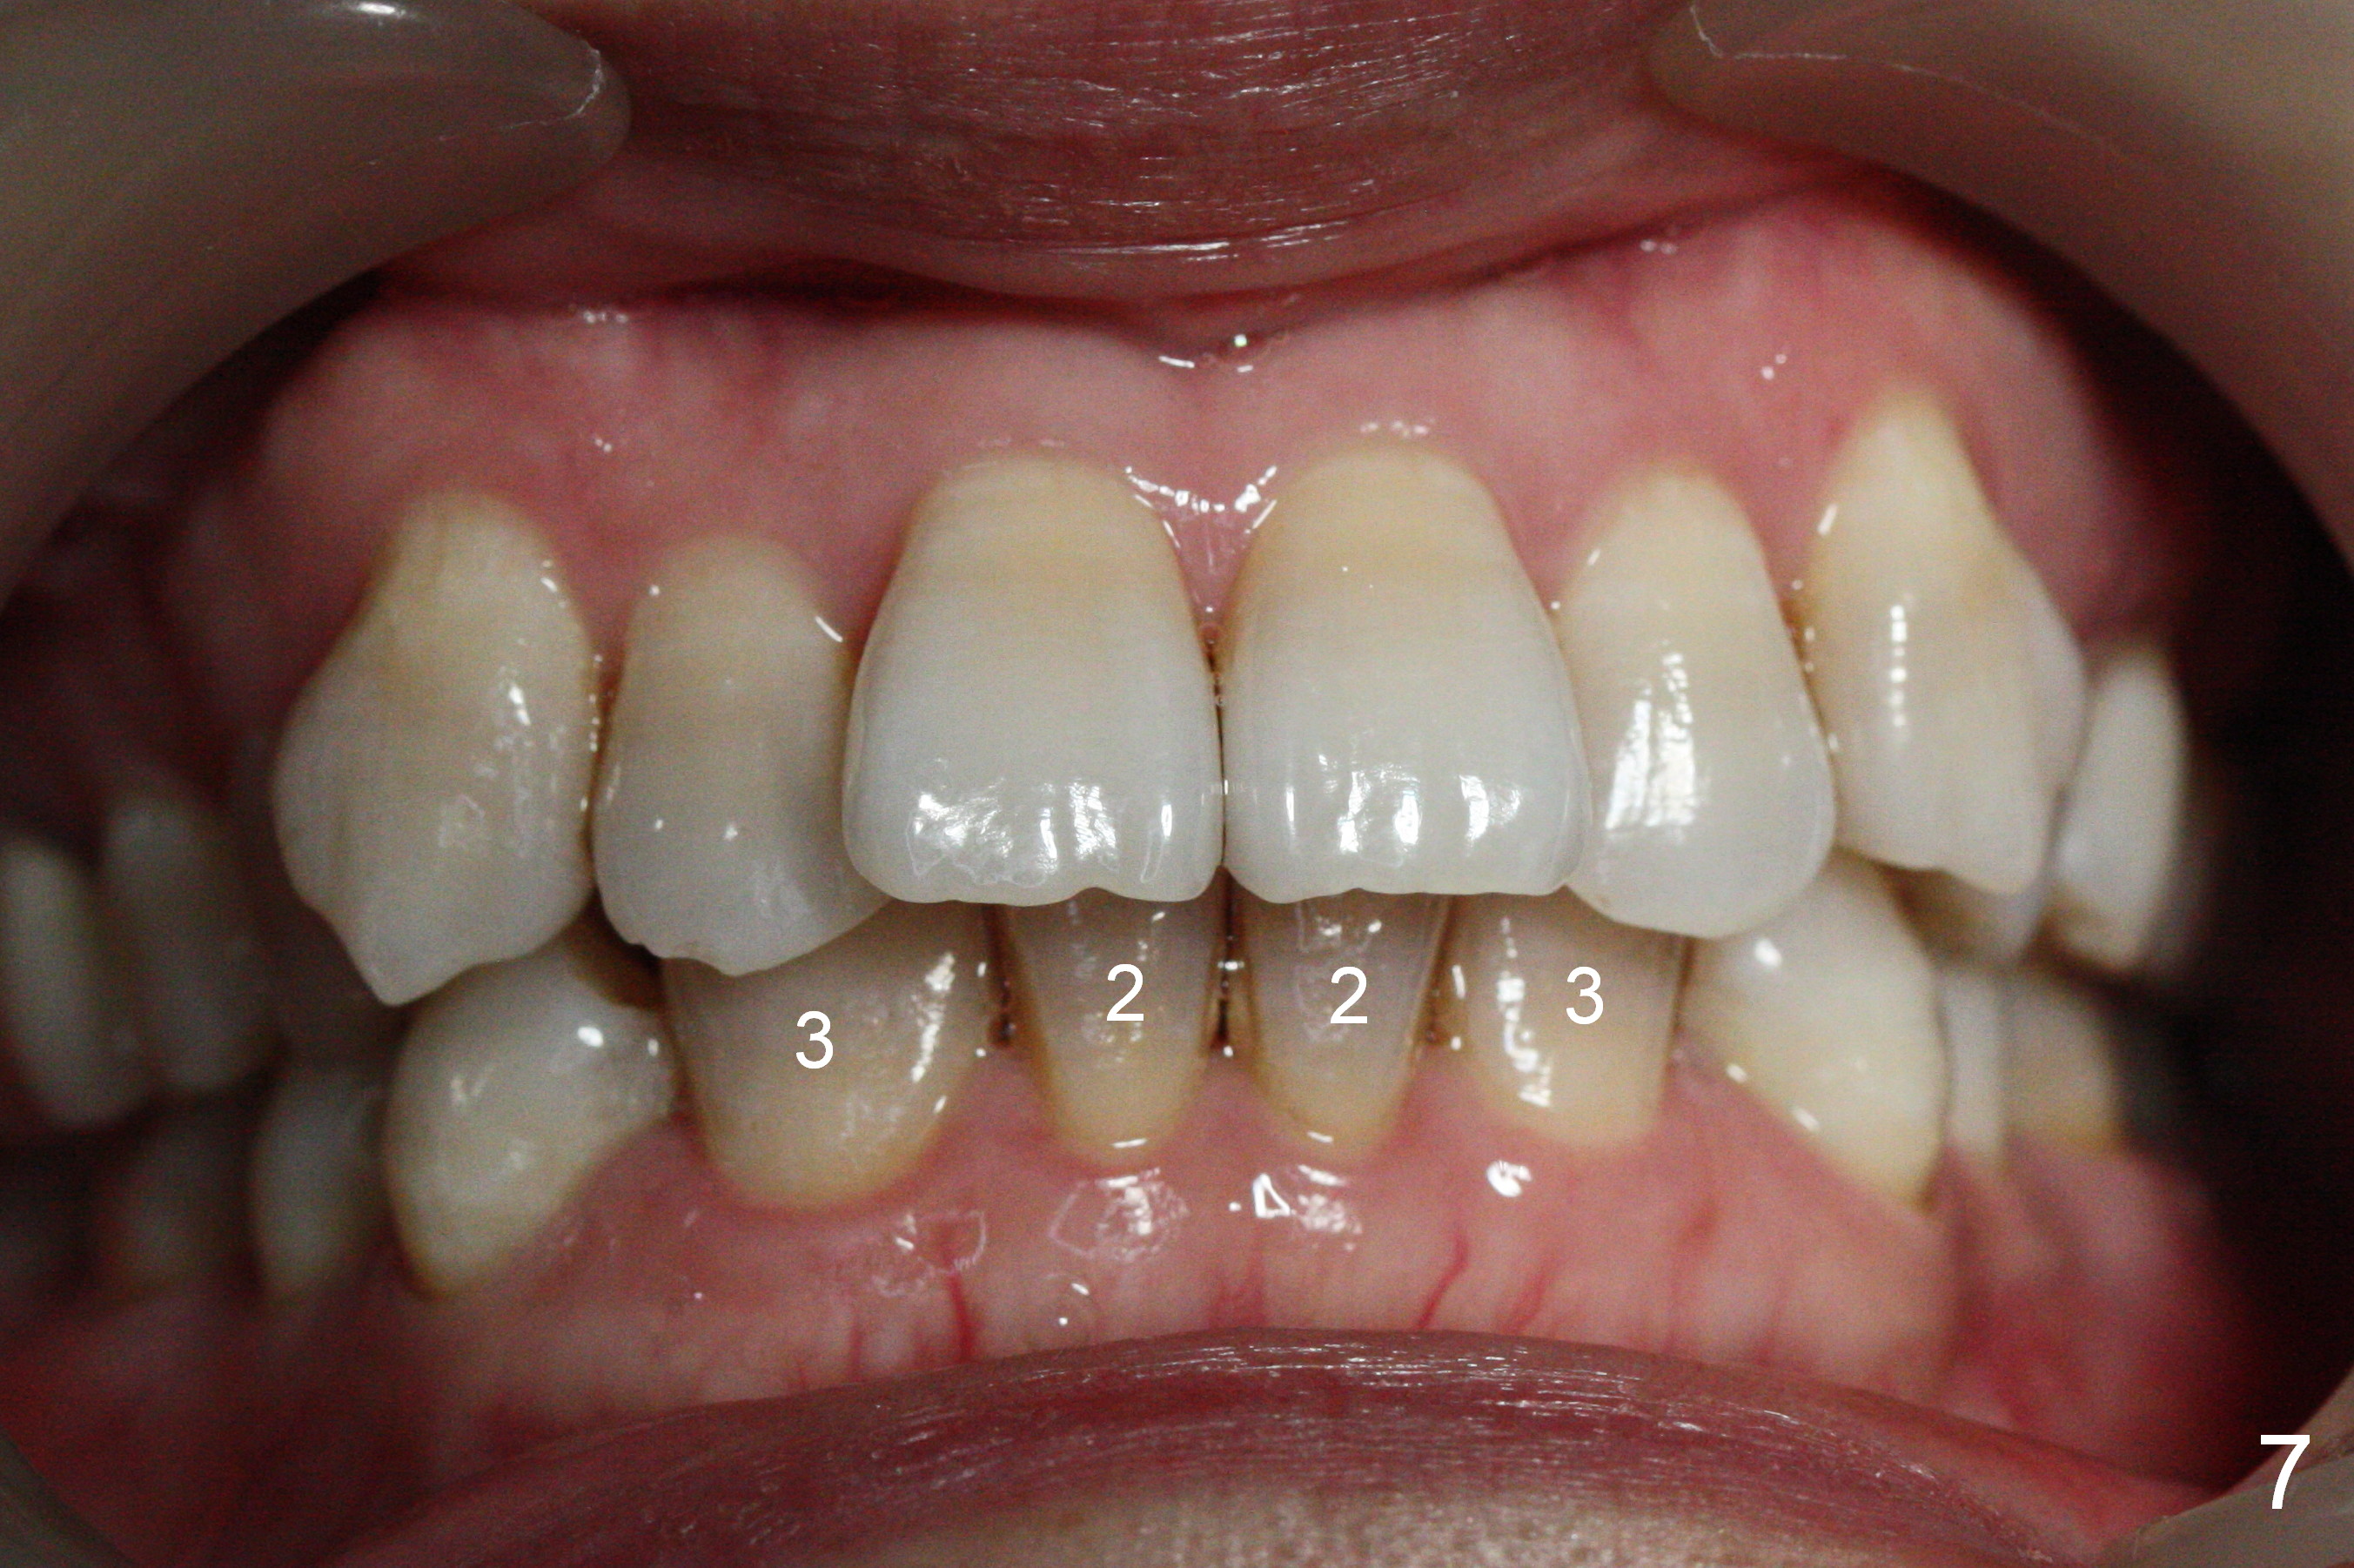

A 41-year-old woman requests orthodontic treatment because of the upper blocked out canines (Fig.6,8). Her facial and dental midlines coincide (Fig.1). Her profile is slightly convex (Fig.2,3) with increase in overjet (Fig.4). Orthodontic treatment includes extraction of U4s and placement of 2 mini-implants between U5 and 6 (Fig.5 o) when arch wires change to 18x25. Power arms (as high as possible) are placed between U2 and 3. U1-3s are retracted at the same time (en mass) because of absolute anchorage of the mini-implants. Retraction time will be reduced. Interproximal reduction (IPR) will be done especially at LR3 (macrodontia, Fig.5) if the lower arch turns out to be too large.

The rotation of the upper canines is not corrected much in the next 3.5 months (Fig.21, as compared to Fig.18). Distalization of the upper right canine is implemented by power chain, but this is not sufficient because of the anterior deep bite. Note the tension of 18 niti wire between LR 3 and 4 (^). Mini implants are going to be placed mesial or distal to L3s (Fig.22,23 circles) to intrude the lower anterior teeth with elastic or power chain (Fig.23 red line, 24 black area). The upper anteriors will have space to be distalized (Fig.24 arrow). If necessary, proximal reduction will be accomplished at LR3 (extra wide, Fig.25 black outline) for further overjet correction (arrows).

Eight months post banding, UR3 appears to be distalized with de-rotation (Fig.26), while UL3 is slightly over-distalized with mesial space (Fig.27 arrow). LL5 remains rotated (Fig.28). One months later, anterior over bite and over jet seem to be normal. In spite of lack of Class I anterior occlusion, it is decided that the upper posterior teeth should be mesialized. Next visit, wires will be changed to 16x16 with ligature wire between U3-3 and power chains between U3 and 5.